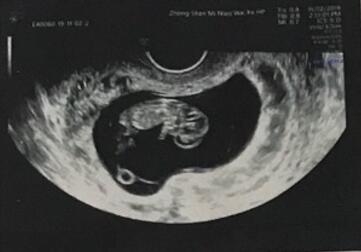

就这样,在做了宫腹腔镜手术,处理了输卵管积水,宫腔粘连之后,我移植了一个囊胚,第一次开奖就怀了,耿妈妈仔细跟我分析情况,交待我怎么保胎;按时回来医院做一超、二超、三超检查。心态放好的我在后续的这些检查里都挺顺利的。感谢遇到耿妈妈,给我送来了宝宝!